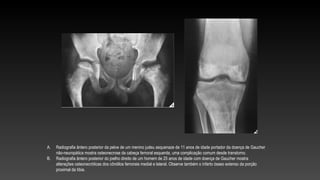

A. Radiografia ântero posterior da pelve de um menino judeu asquenaze de 11 anos de idade portador da doença de Gaucher

não-neuropática mostra osteonecrose da cabeça femoral esquerda, uma complicação comum desde transtorno.

B. Radiografia ântero posterior do joelho direito de um homem de 25 anos de idade com doença de Gaucher mostra

alterações osteonecróticas dos côndilos femorais medial e lateral. Observe também o infarto ósseo extenso da porção

proximal da tíbia.